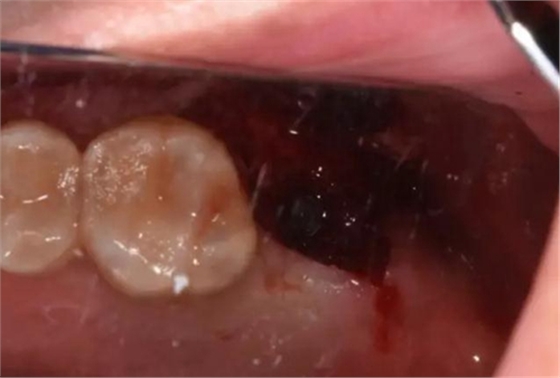

二期手術術中照